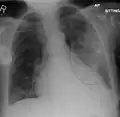

AP CXR showing left lower lobe pneumonia associated with a small left sided pleural effusion

AP CXR showing right lower lobe pneumonia

AP CXR showing pneumonia of the lingula of the left lung

Right upper lobe pneumonia as marked by the circle.

Left upper lobe pneumonia with a small pleural effusion.